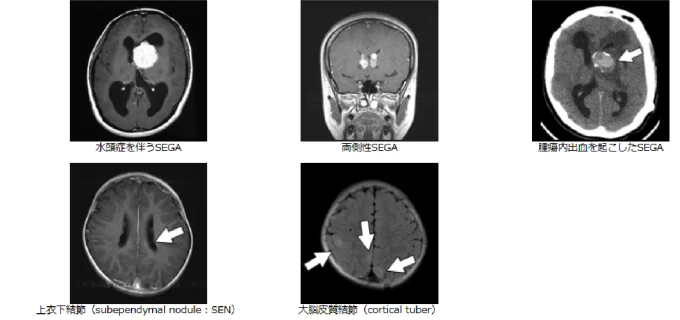

結節性硬化症に伴う神経病変としては,SEGAの他,大脳皮質結節(cortical tuber),上衣下結節(subependymal nodule:SEN),放射状大脳白質神経細胞移動線が知られているが,臨床上SENとSEGAの鑑別が重要である(図1)。SEGAの画像診断基準(表2)は,「尾状核視床溝(caudothalamic groove)も含むモンロー孔近傍に位置する病変で,(1)最大径1cm以上,(2)経時的に増大する上衣下腫瘍(造影効果の有無を問わない)」となっている1)。通常SEGAでは著しい造影効果を示すが,増大傾向を示す上衣下病変では造影効果がなくともSEGAとみなすべき点に注意を要する。

図1 結節性硬化症に伴う神経病変の画像所見